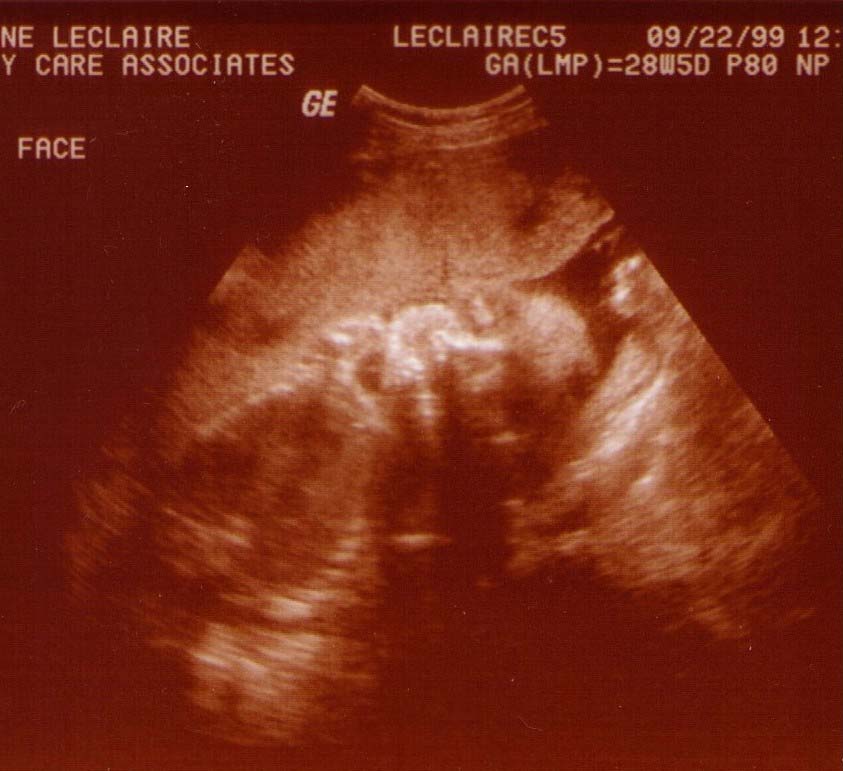

Alexander James LeClaire

Ultrasound Pics!